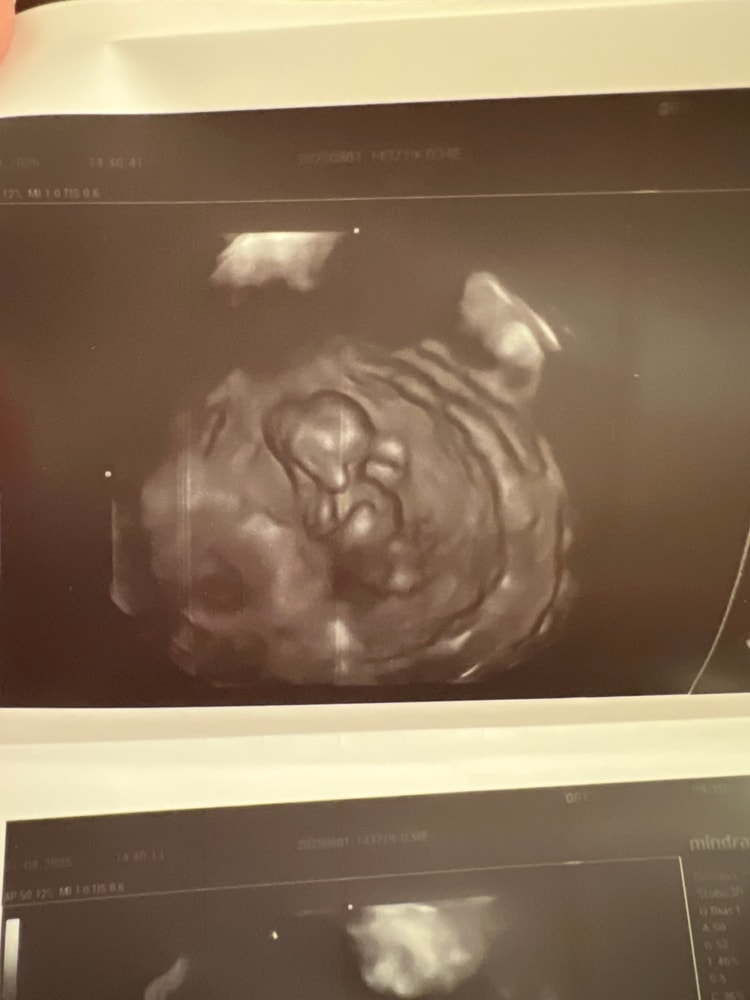

УЗИ 11 недель

УЗИ, КТГ, доплерНеделю болела,пришлось пить антибиотики,после того как вылечилась соотвественно побежала смотреть малышарика.Сегодня поставили срок по узи 11 недель,врач сделала мне 3д снимки черно белые ,я посмотрела на снимок и ничего не поняла кроме рук и ног😇Но главное что сказали что все хорошо.Кто нибудь делал такие снимки на таком раннем сроке?Приложу фото может кому будет интересно)

Ryabina, целых 4,5 см человек))На экран тоже выводила,как будто на экране понятнее было)))